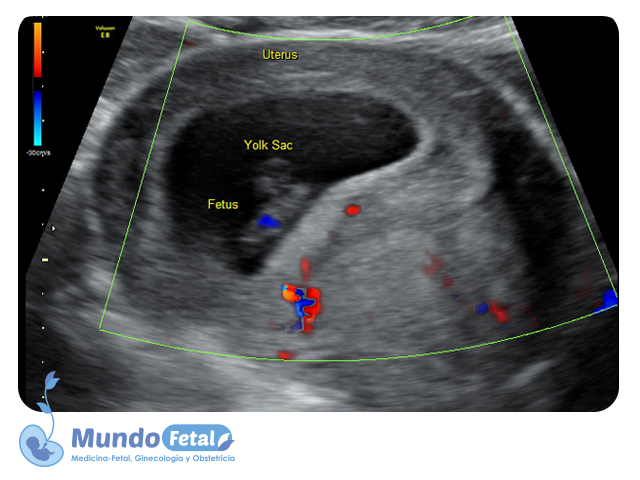

Ultrasonido Temprano 1er Trimestre (Menor 11 Semanas)

Estudio que nos permite la confirmación del embarazo, numero de bebes, valoración de líquido amniótico, placenta, vitalidad por medio de la frecuencia cardiaca, crecimiento armónico y edad gestacional estimada, descartando alguna complicación propia de esta edad.